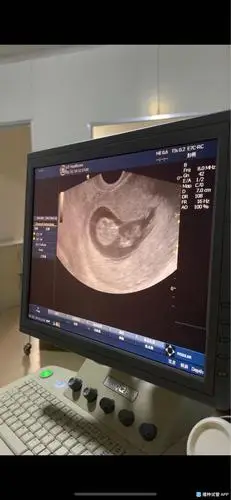

怀孕10周小孩成型图片 10张图胎儿发育成型全过程

从头到臀部长3.4cm 体重约8.5g,如图所示7070:两胎儿的发育情况

[试管婴儿]孕10周 1,宝宝在肚子里活蹦